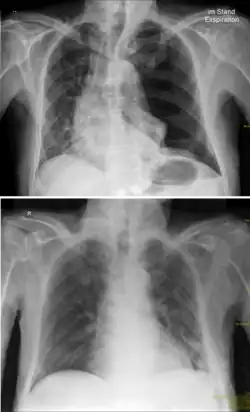

Der Spannungspneumothorax ist eine besondere und lebensgefährliche Form des Pneumothorax. Er entsteht, wenn Luft durch eine Verletzung in den Pleuraspalt eindringt, ohne wieder entweichen zu können. Bei der Einatmung (Inspiration) kann Luft entweder von außen (z. B. durch einen Einstich) oder von innen (z. B. durch einen eingerissenen Lungenlappen) in den Pleuraspalt gelangen. Bei der Ausatmung (Exspiration) wird die Verletzung von innen zugedrückt, wie bei einem Rückschlagventil, so dass die Luft nicht mehr entweichen kann und sich stattdessen im Pleuraspalt verteilt. Deshalb wird diese Verletzung auch als Ventilpneumothorax bezeichnet. Mit Zunahme des Luftvolumens steigt der intrathorakale Druck auf der verletzten Seite an und verdrängt das Mittelfell zur Gegenseite. Auf diese Weise werden die gesunde Lunge und die Hohlvenen komprimiert. Die Venenkompression drosselt den venösen Rückstrom zum Herzen, wodurch das Schlagvolumen bedrohlich abnimmt.

Entsteht durch ein Thoraxtrauma eine Verbindung zwischen Außenluft und Pleuraspalt, so kollabiert der betroffene Lungenflügel. Im Unterschied zu einem „normalen“ Pneumothorax entweicht die Atemluft bei der Exspiration jedoch nicht wieder aus dem betroffenen Gebiet, sondern verbleibt aufgrund eines Ventilmechanismus im sich nun immer mehr weitenden Pleuraspalt. Bei der Einatmung gelangt Luft zwischen Lungengewebe und Rippenfell (Pleura visceralis und Pleura parietalis). Bei der Exspiration wird nun nach und nach mehr Luft in den intrathorakalen Raum gepresst, was eine Erhöhung des intrathorakalen Drucks zur Folge hat. Dies führt zu einer Verdrängung des Mittelfells (Mediastinums) und auch des Herzens. Diese Verdrängung des Herzens wiederum führt zu einem behinderten venösen Rückfluss (Abknicken der Vena cava inferior und superior). Auch wird der ansonsten intakte Lungenflügel der gegenüberliegenden Seite komprimiert, was eine Minderversorgung mit Sauerstoff nach sich zieht. Man unterscheidet zwischen einem offenen (Verbindung durch ein Loch in der Brustwand) und geschlossenem (Verbindung durch Riss in der Lunge) Spannungspneumothorax.